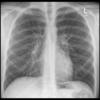

Normal PA Male

Date: 12/06/2014

Views: 6539